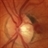

- Unusual presentation of VHL juxtapapillary hemangioblastoma detached from retina with feeder vessels

- Von Hippel-Lindau, retinal hemangioblastoma

- 30-year-old female with fhx VHL and CNS hemangioblastomas and visceral lesions. P/C with a floater (no PVD or VH) after episodes of vomiting.